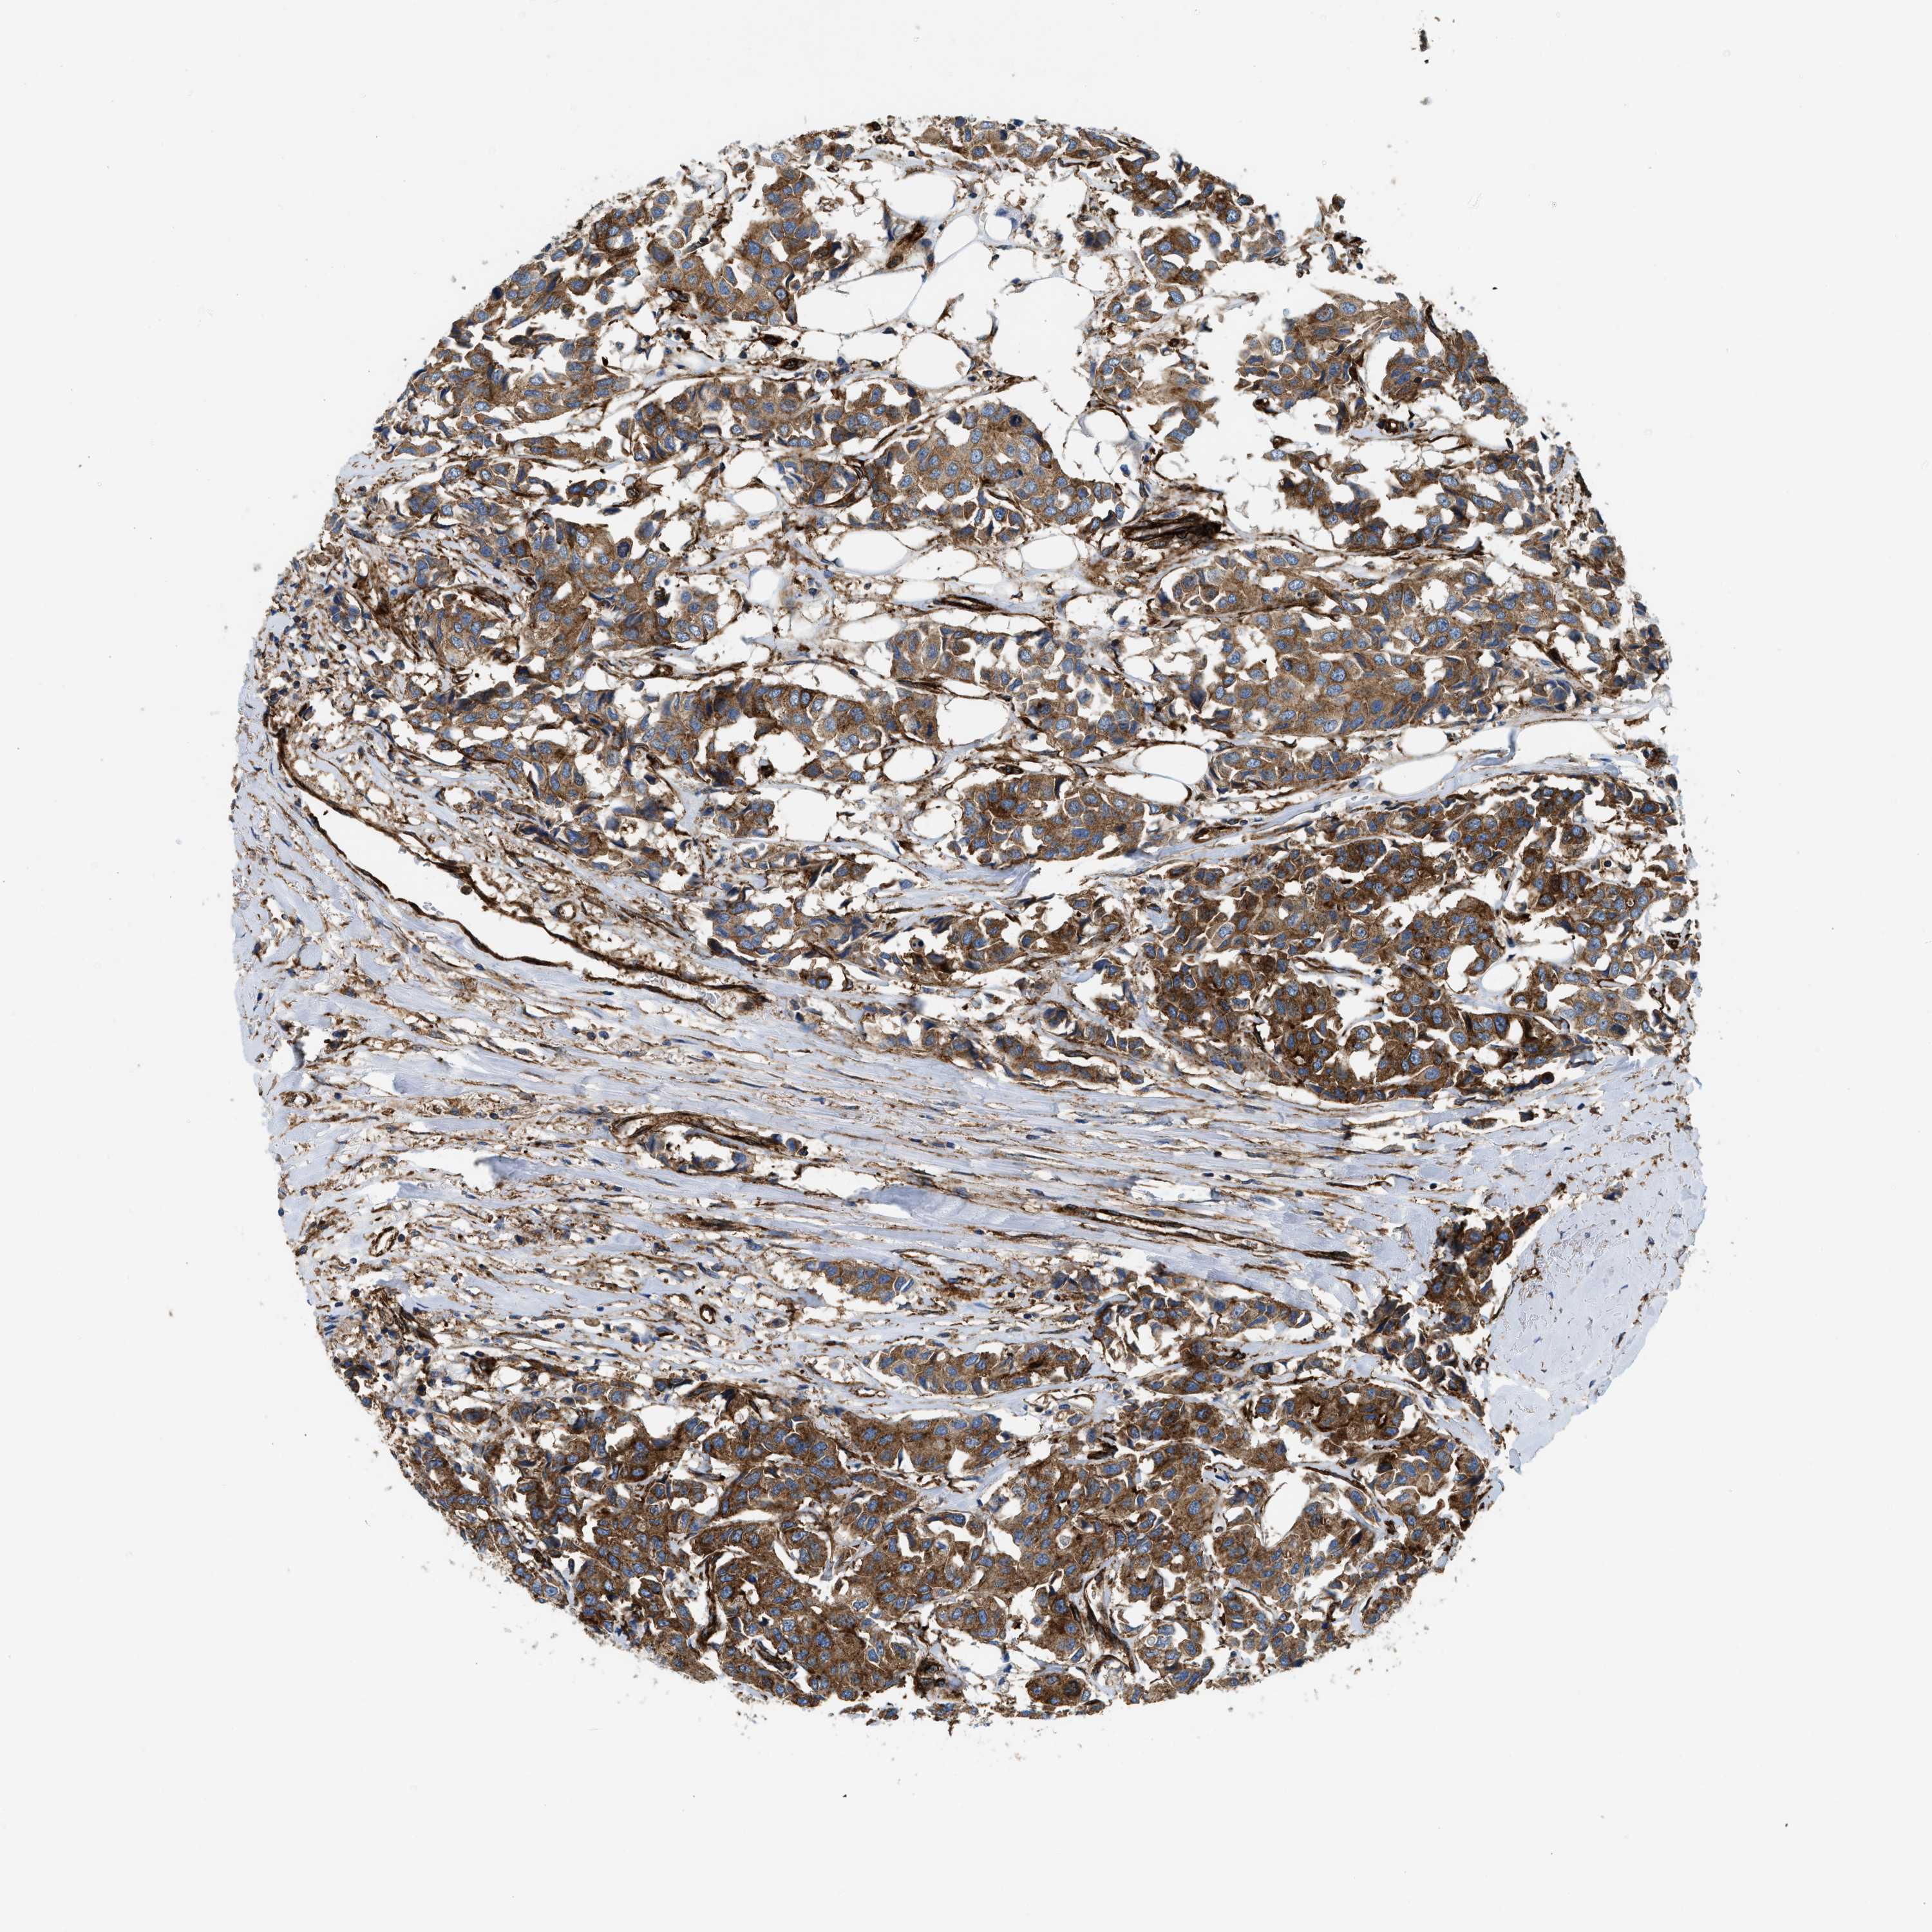

CANCER BREAST CANCER Show tissue menu

BRCA TCGA BRCA VALIDATION PROTEIN EXPRESSION

ANTIBODIES

AND

VALIDATION